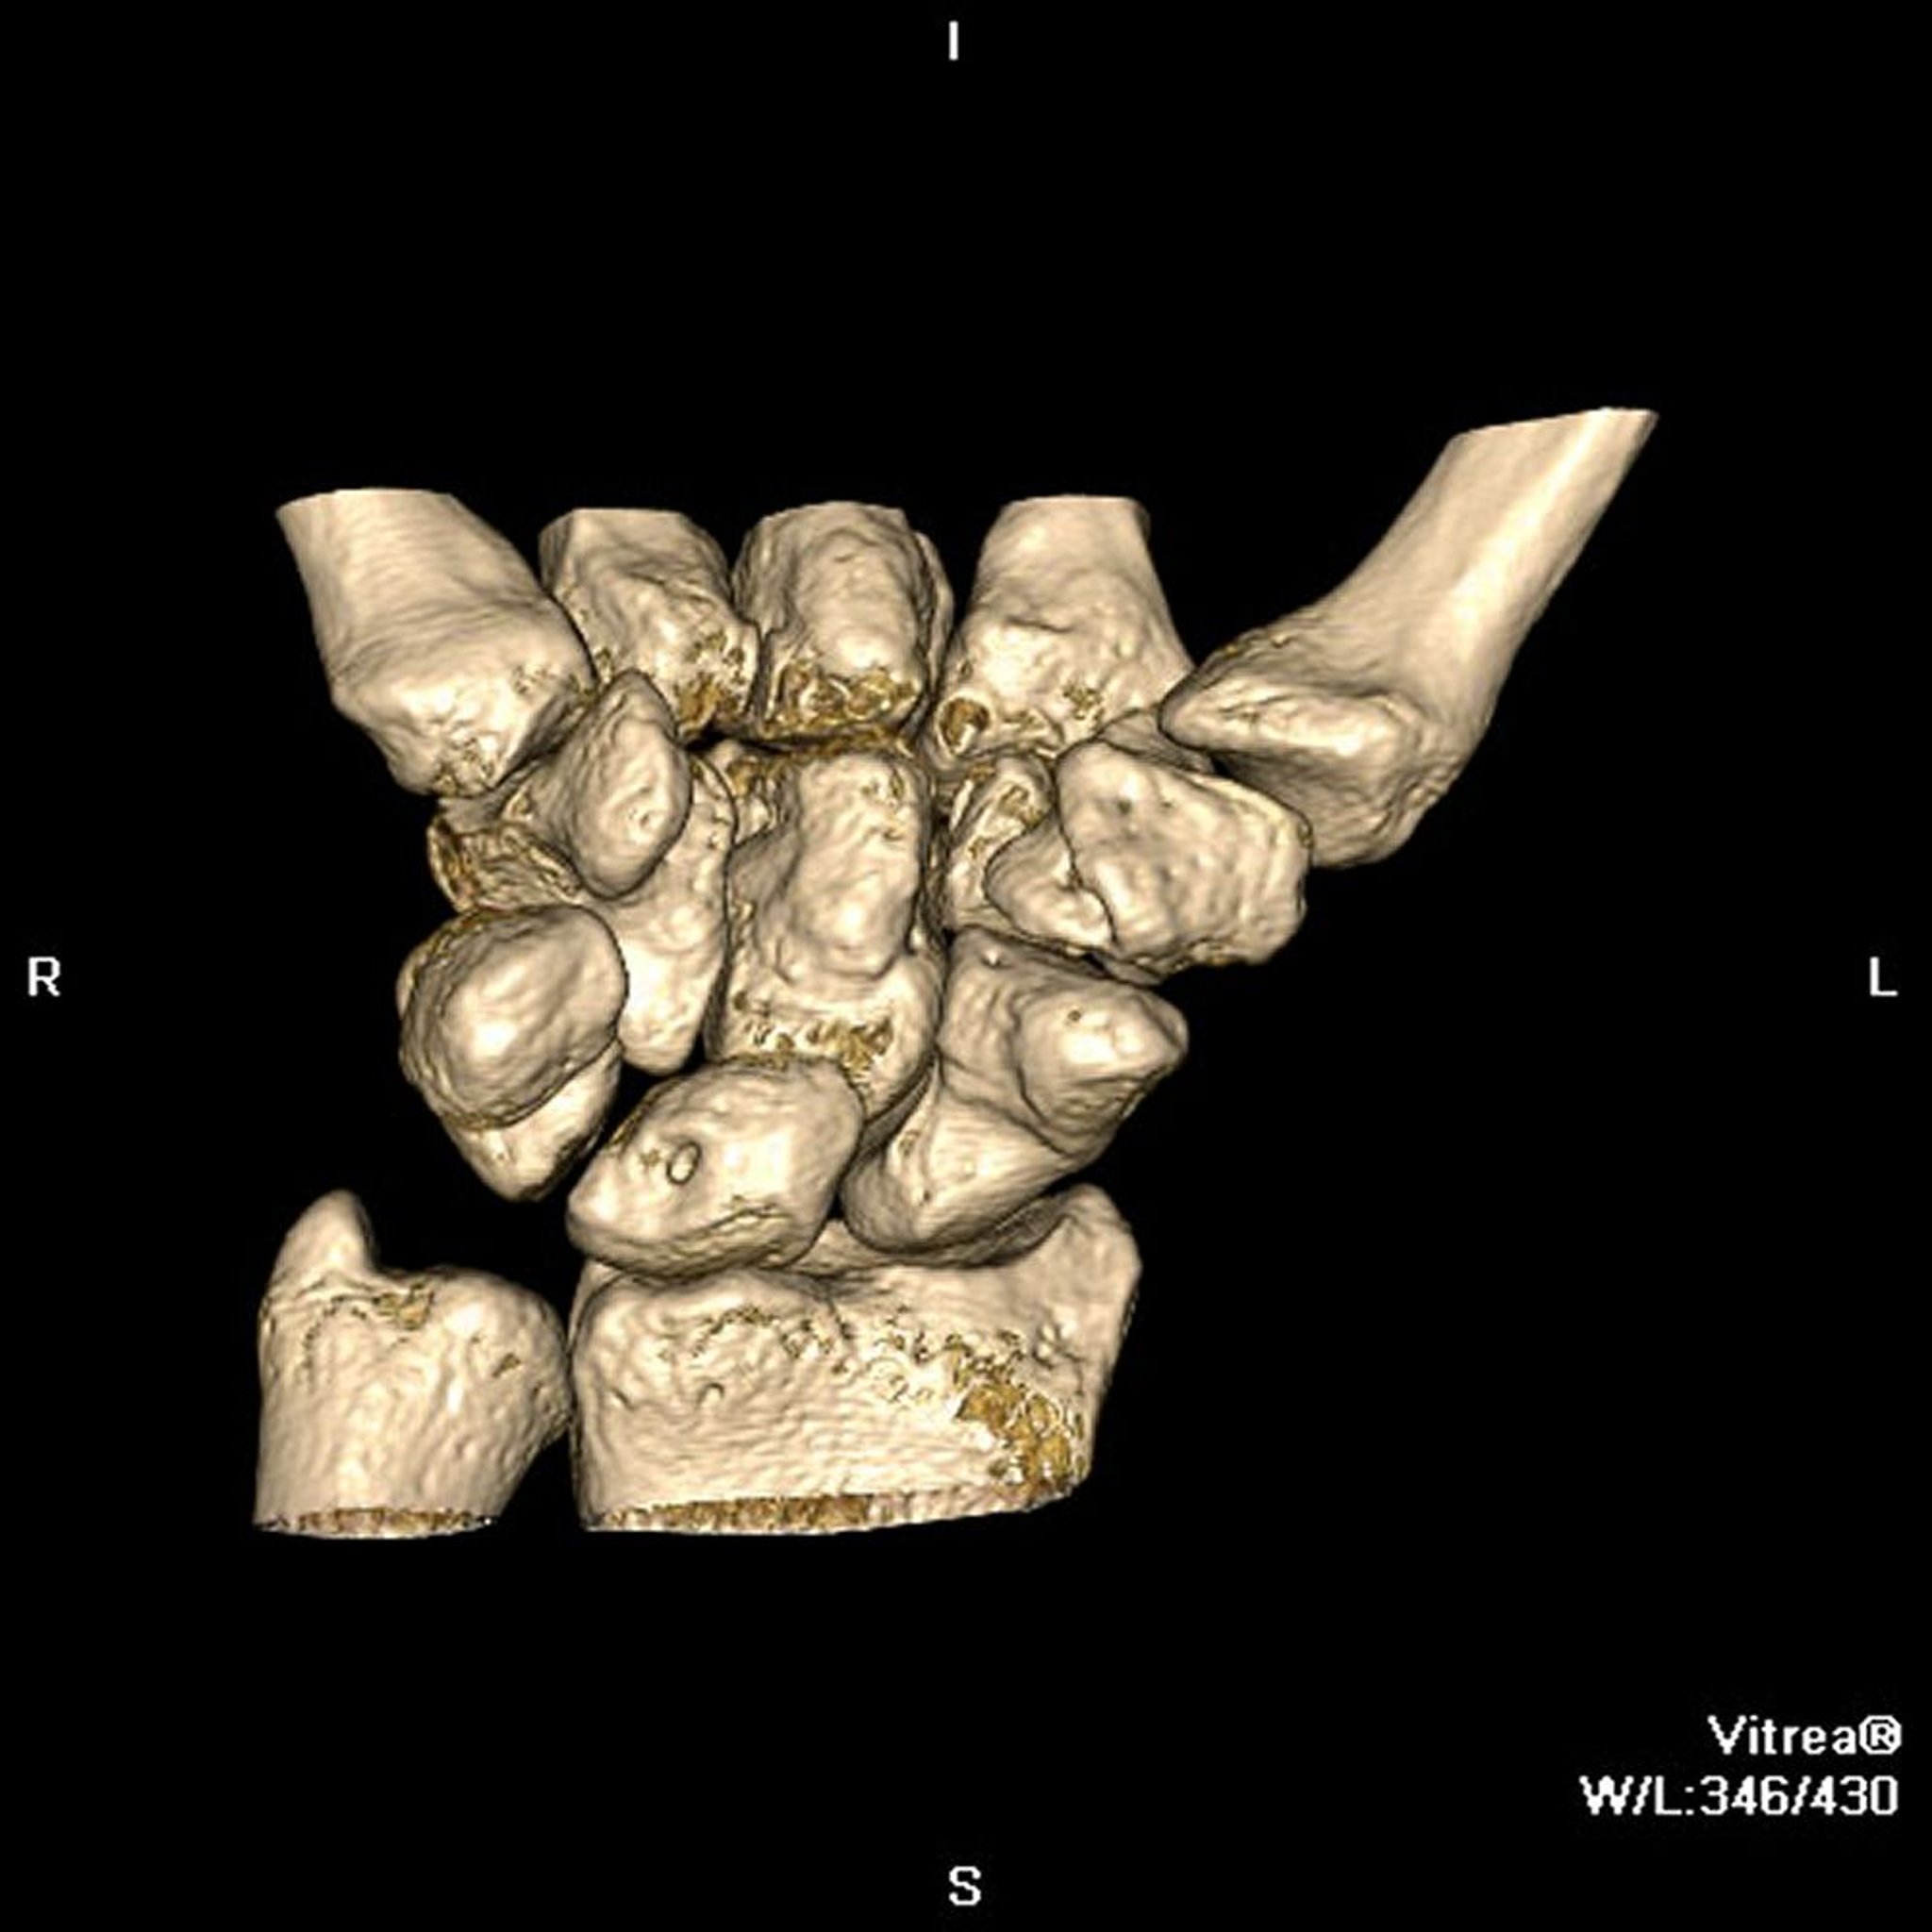

कंप्यूटेड टोमोग्राफ़ी (CT) में, जिसे कंप्यूटेड एक्सियल टोमोग्राफ़ी (CAT) कहा जाता था, एक एक्स-रे सोर्स और एक्स-रे डिटेक्टर व्यक्ति के चारों ओर घूमते हैं। आधुनिक स्कैनरों में, एक्स-रे डिटेक्टर में आमतौर पर सेंसर की 4 से 64 या अधिक पंक्तियां होती हैं जो शरीर से होकर गुज़रने वाली एक्स-रे को रिकॉर्ड करती हैं। सेंसर से मिलने वाला डेटा, व्यक्ति के चारों ओर कई कोणों से लिए गए एक्स-रे मेज़रमेंट को दर्शाता है। हालांकि, ये मेज़रमेंट सीधे देखे जाने के बजाय कंप्यूटर पर भेजे जाते हैं। कंप्यूटर उन्हें इमेज में बदलता है जो शरीर के 2-डायमेंशनल स्लाइस (क्रॉस-सेक्शन) जैसा दिखता है। कंप्यूटर, रिकॉर्ड की गई इमेज से 3-डायमेंशनल इमेज भी बना सकता है।

CT एंजियोग्राफ़ी में CT और एक रेडियोपैक कंट्रास्ट एजेंट का इस्तेमाल करके रक्त वाहिकाओं की 2- और 3-डायमेंशनल इमेज बनाई जाती हैं, जिनमें वो धमनियां भी शामिल हैं (कोरोनरी धमनियां) जो हृदय में रक्त की आपूर्ति करती हैं। कंट्रास्ट एजेंट को आमतौर पर बांह में एक नस (बरसों से की जाने वाली एंजियोग्राफ़ी की तरह धमनी में नहीं) में इंजेक्ट किया जाता है। इन इमेज को तेज़ी से लिया जाता है और इमेज पर समय भी डाला जाता है ताकि मूल्यांकन की जा रही रक्त वाहिकाओं से होकर बहने वाले रेडियोपैक कंट्रास्ट एजेंट को इन इमेज में दिखाया जा सके। कंप्यूटर इन इमेज से सभी ऊतकों को डिजिटल रूप से हटा देता है, रक्त वाहिकाओं को छोड़कर। (कोरोनरी एंजियोग्राफ़ी भी देखें।)